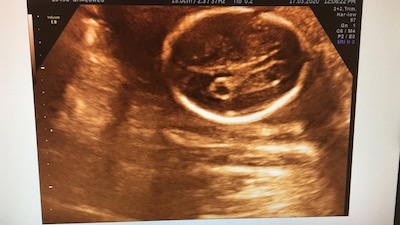

Bu yapıların içindeki sıvı dolu oluşumlara koroid pleksus kisti denir. Gebeliklerin ortalama % 2’sinde görülür.Koroid pleksus kistlerinin (KPK )nedeni bilinmemektedir. Hiperekojenik koroid pleksuslar içerisinde sonolusen olarak görülen kistler, genellikle 10 mm altında olmak üzere farklı büyüklükte olabilir. Yine sağ veya koroid pleksuslar içinde tek yada çift taraflı olabilir. 14. gebelik haftasından sonra tanınabilir genellikle 17-18.hf da tanı alırlar.

Koroid pleksus kistinin ultrasonografi ile tanısı konduğunda; koroid pleksus papillomu, hafif ventrikülomegali ve kafa içi kanamalarından da ayırt edilmesi önemlidir.

Bebekte beyin kisti (KPK) normal gebeliklerin de %2'sinde ultrason muayensine sırasında tespit edilebilir. Kistler genellikle gebelik ilerledikçe genellikle kaybolurlar. Bebeğin beyin gelişimini veya zekasını etkilemezler. %90'dan fazlası 28. gebelik haftasına kadar kaybolur ve tekrar oluşmazlar. Literatürde 31 haftaya kadar görülenler olmakla beraber 32. gebelik haftasından sonra devam ediyorsa diğer patolojiler ayırt edilmelidir.